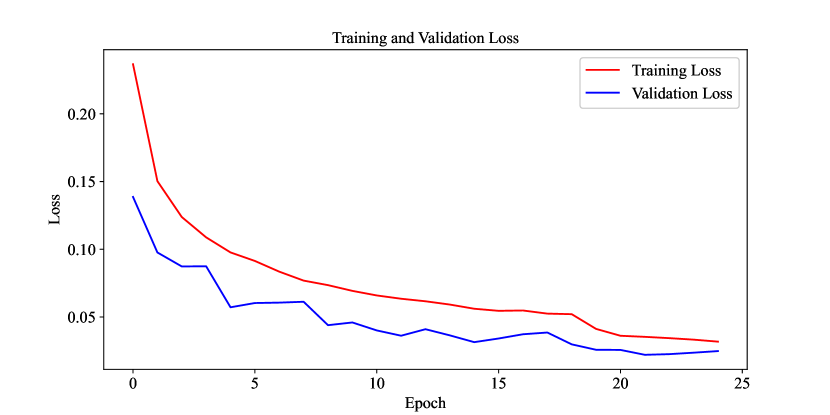

The results of the multi-label classification for cervical spine vertebrae demonstrate the performance of various neural network models. The proposed network, with a MacroF1 score of 0.96 and an Exact Match Ratio of 0.95, exhibits promising results when compared to other models, including ViT, Convext, InceptionV3, ResNet152V2, and Swin Transformer. Table 2 displays the classification report for the proposed network, illustrating its strong performance in multi-label cervical spine vertebrae classification. The network achieves high precision (0.97 to 1.00), recall (0.93 to 0.98), and F1-scores (0.95 to 0.99) across all seven classes (C1 to C7), indicating its effectiveness in correctly identifying vertebrae. The micro, macro, and weighted averages are all approximately 0.97, showing consistent overall performance. The loss diagram of the proposed network is also presented in Figure 6, revealing a consistent downward trend over the course of 25 training epochs.